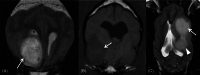

Results: No associations were found between clinicopathologic findings or survival and tumor type or grade. However, definitive treatments provided significantly (P = .03) improved median survival time (84 days; 95% confidence interval [CI], 45-190) compared to palliative treatment (26 days; 95% CI, 11-54). On magnetic resonance imaging (MRI), oligodendrogliomas were associated with smooth margins and T1-weighted hypointensity compared to astrocytomas (odds ratio [OR], 42.5; 95% CI, 2.42-744.97; P = .04; OR, 45.5; 95% CI, 5.78-333.33; P < .001, respectively) and undefined gliomas (OR, 84; 95% CI, 3.43-999.99; P = .02; OR, 32.3; 95% CI, 2.51-500.00; P = .008, respectively) and were more commonly in contact with the ventricles than astrocytomas (OR, 7.47; 95% CI, 1.03-53.95; P = .049). Tumor spread to neighboring brain structures was associated with high-grade glioma (OR, 6.02; 95% CI, 1.06-34.48; P = .04).

Conclusions and clinical importance: Dogs with gliomas have poor outcomes, but risk factors identified in survival analysis inform prognosis and the newly identified MRI characteristics could refine diagnosis of tumor type and grade.